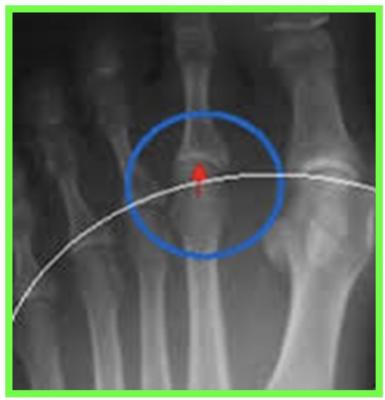

HALLUX RIGIDUS

L’hallux rigidus (ou hallux limitus) est le nom donné à l’arthrose de l'articulation métatarso phalangienne de l’hallux. Il s’agit d’une maladie dégénérative de l’articulation métatarso-phalangienne (MTP) et de la sesamoido métatarsienne, le plus souvent sans cause connue (idiopathique).

DIAGNOSTIC

STADE 1 : HALLUX DOLOROSUS

Pincement de l’interligne

Hallux rigidus au stade de raideurs

STADE 2 : HALLUX LIMITUS

Volumineuse exostose dorsale

Pincement majeur, ostéophytes

On constate cliniquement un aspect globuleux de la MTP de l’hallux, avec une excroissance osseuse (ostéophyte dorsal) gênant le chaussage. Limitation douloureuse de la flexion dorsale de la MTP

Parfois sensation de craquement à la mobilisation de la MTP

L'hallux est le plus souvent normo-axé

QUE FAIRE ?

Radiographie des pieds face et profil en charge +++ avant consultation d’un spécialiste

Étude de l’architecture global du pied, de l’état articulaire à la recherche d’une arthrose, fracture de contrainte, et mesure des angles

Le pincement de l’interligne articulaire et les ostéophytes ci-dessus sont caractéristiques de l’hallux rigidus